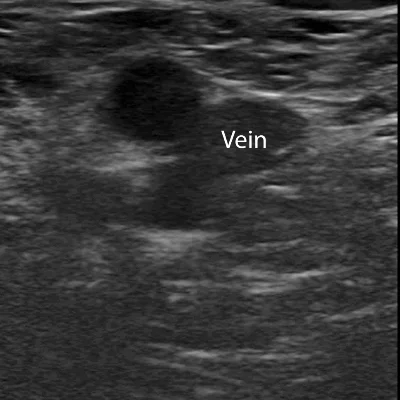

Doppler Ultrasound

Doppler studies assess blood flow in arteries and veins, helping detect

Deep vein thrombosis (DVT)

Peripheral artery disease

Carotid artery narrowing

Placental blood flow in pregnancy

These scans are crucial for vascular health and prenatal monitoring, offering dynamic insights into circulation.